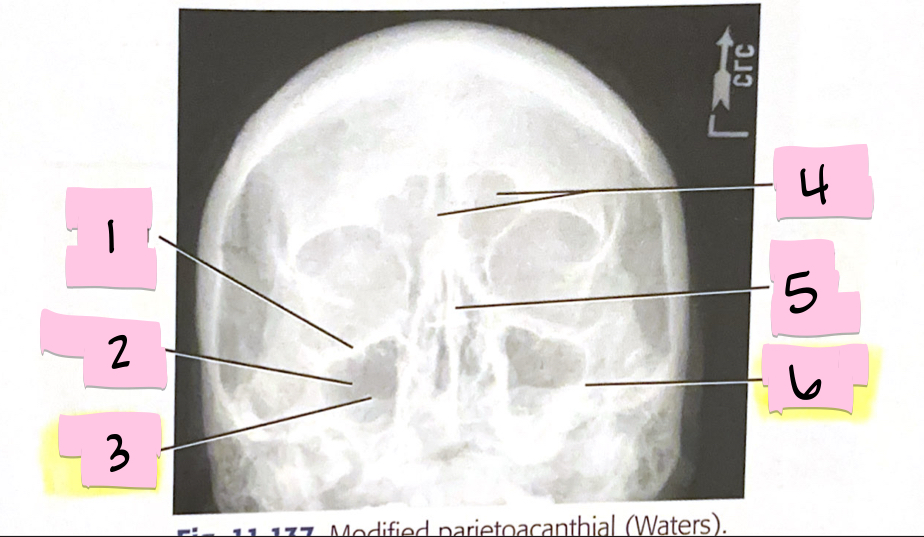

What is 1 pointing to?

Inferior orbital margin

What is 2 pointing to?

Maxillary sinus

What is 3 pointing to?

Petrous ridge

What is 4 pointing to?

Frontal sinuses

What is 5 pointing to?

Bony nasal septum

What is 6 pointing to?

Petrous ridge